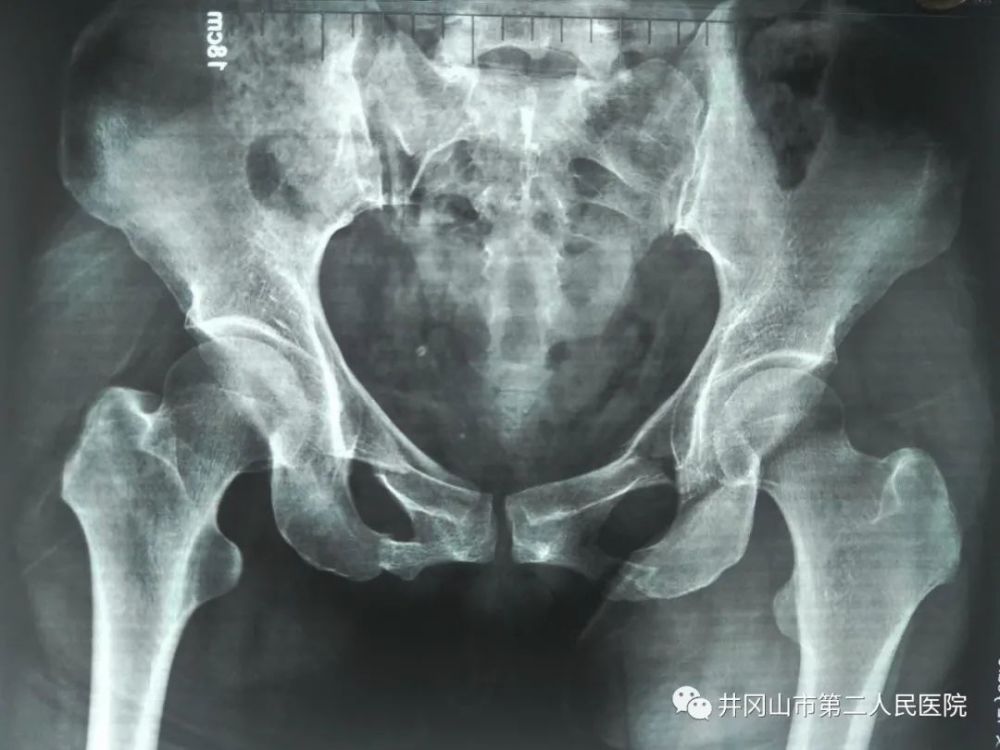

一例多发骨折治疗方式探讨

图片尺寸2560x1920